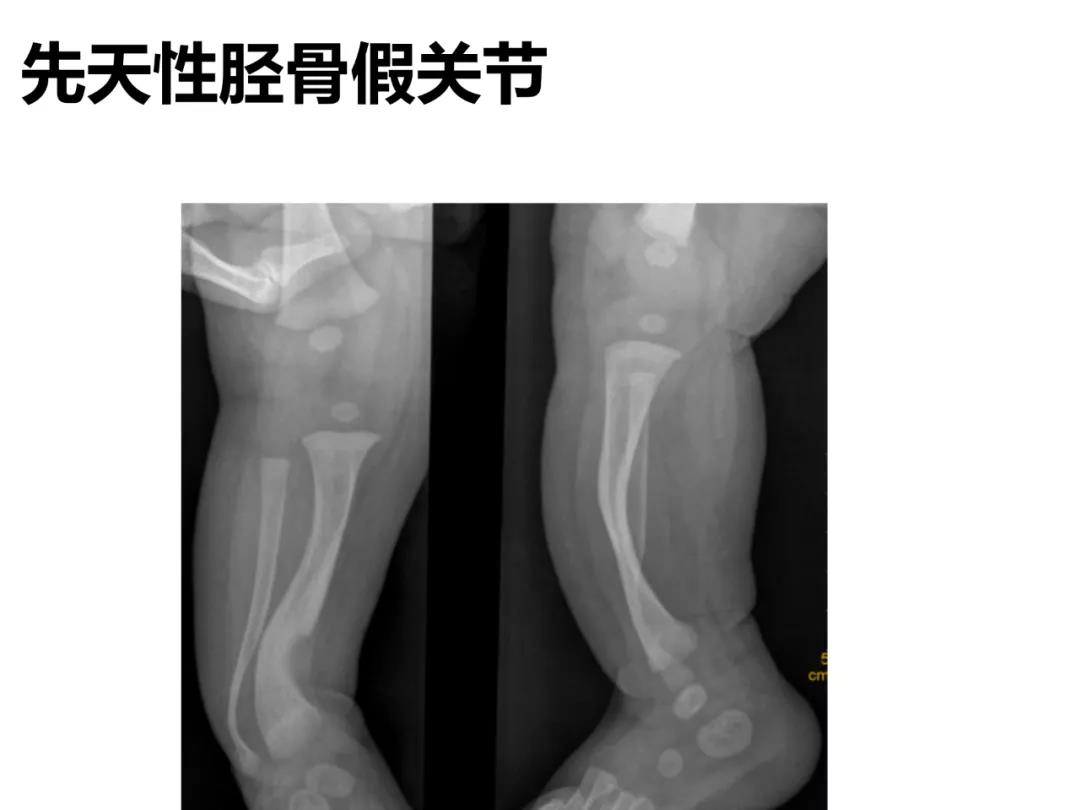

小儿骨科X线片汇总,临床读片宝典!